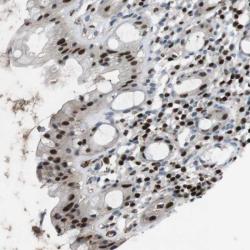

- Experimental details

- Immunohistochemical staining of human rectum shows strong nuclear positivity in glandular cells.

- Validation comment

- Two independent antibodies targeting one protein yielding similar staining patterns. Staining pattern consistent with experimental and/or bioinformatic data.